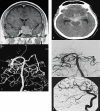

Vascular injury is an unusual and serious complication of transsphenoidal surgery. We aimed to define the role of angiography and endovascular treatment in patients with vascular injuries occurring during transsphenoidal surgery. During the last ten-year period, we retrospectively evaluated nine patients with vascular injury after transsphenoidal surgery. Eight patients were symptomatic due to vascular injury, while one had only suspicion of vascular injury during surgery. Four patients presented with epistaxis, two with subarachnoid hemorrhage, one with exophthalmos, and one with hemiparesia. Emergency angiography revealed a pseudoaneurysm in four patients, contrast extravasation in two, vessel dissection in one, vessel wall irregularity in one, and arteriovenous fistula in one. All patients but one were treated successfully with parent artery occlusion, with one covered stent implantation, one stent-assisted coiling method, while one patient was managed conservatively. One patient died due to complications related to the primary insult without rebleeding. Vascular injuries suspected intra or postoperatively must be investigated rapidly after transsphenoidal surgery. Endovascular treatment with parent artery occlusion is feasible with acceptable morbidity and mortality rates in the treatment of vascular injuries occurring in transsphenoidal surgery.